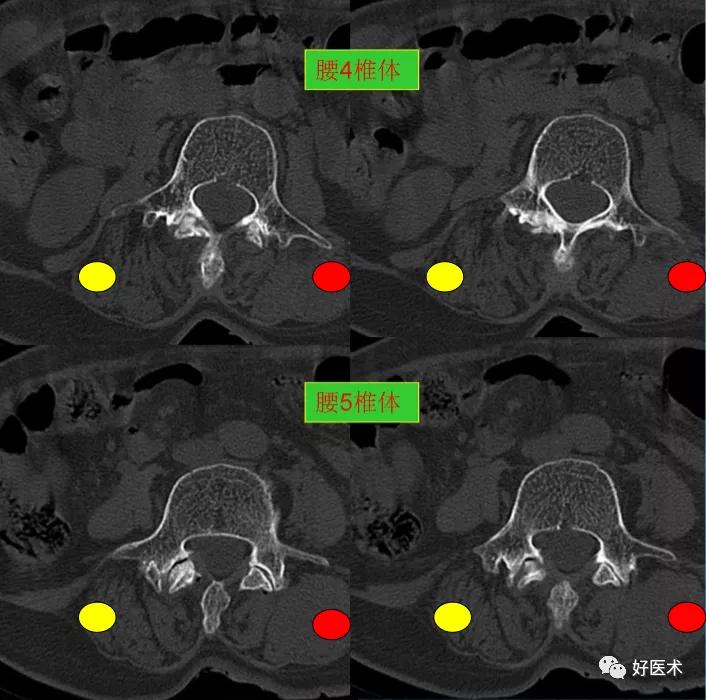

发现了什么?左侧竖脊肌较右侧明显肿胀饱满, 肌间脂肪间隙消失!!

可以想到的原因:

- 外伤。

- 感染(普通或特异性炎症)。

- 肿瘤(原发、继发)。

终于知道了是什么鬼在作乱, 找到了左侧竖脊肌肿胀的元凶:肺癌转移。

1.观察出现盲区:腰椎检查仅侧重于观察腰椎体及附件骨质、 腰椎间盘、椎管情况,忽略了对周边肌肉策划的观察,这是漏诊的根本原因。